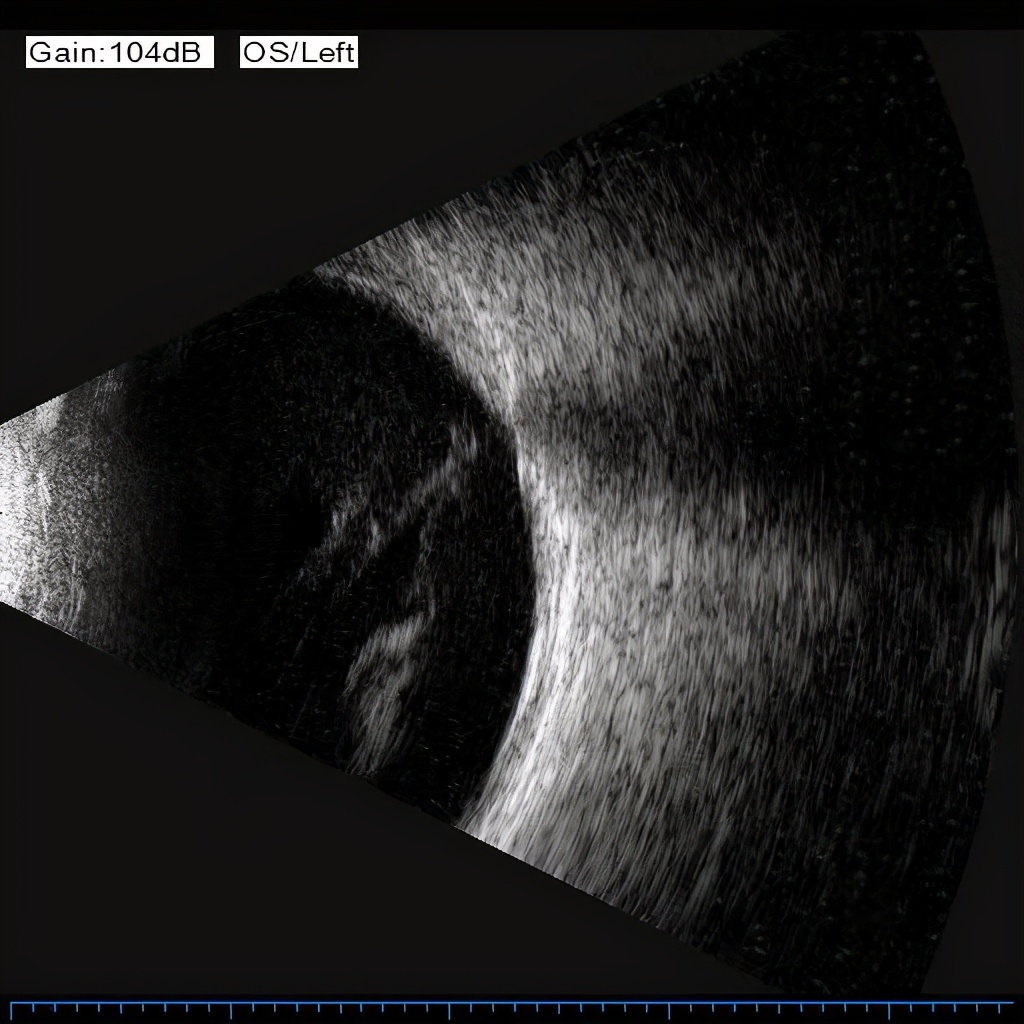

2月18日,刘先生回汉后第一时间求助杜磊副教授。“我感觉这次左眼发病来的更急更猛。从年初到现在,我是一丁点都看不到,特别怕一辈子就这样了……” 刘先生回想起来仍心有余悸。在眼科中心门诊,经过超广角眼底照相、眼B超、OCT等专业检查,刘先生被确诊为左眼严重增殖性糖尿病视网膜病变(Ⅳ期)、玻璃体积血并伴有黄斑水肿。

由于患者左眼玻璃体出血已近半年,眼底情况复杂,手术难度较大,同时患有II型糖尿病,手术后易感染。为避免较大的手术创伤,降低手术并发症发生率,经眼科中心专家团队多次研究讨论后,杜磊医生决定使用世界最先进的25G微创玻切手术“黑科技”——10000切速超高速斜面万能玻切头为他实施手术。